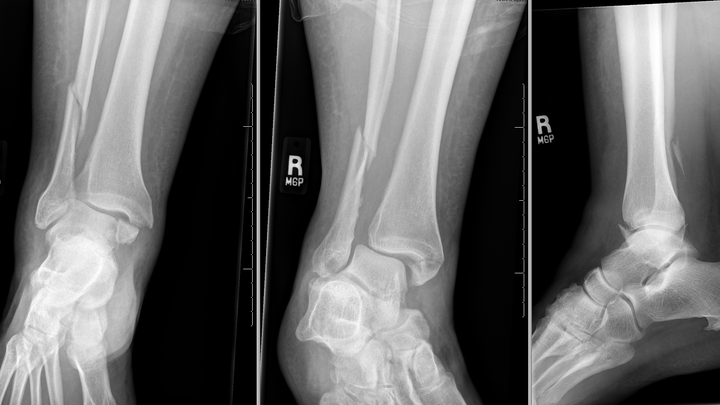

Hello, and thank you for taking the time to read this. My name is Rhena, and on February 4th, I slipped and broke both the tibia and fibula of my right leg near the ankle as I was walking to work. I have been off work since, and will be for the next few months. I am working on getting on temporary disability, but I have rent and bills coming up in a few weeks and need assistance. I greatly appreciate any help you can offer, whether it's $5 or just sharing my gofundme.